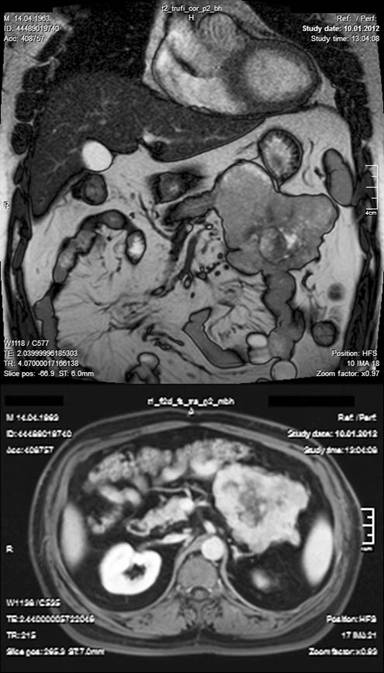

We report the case of a forty-eight year-old man with a giant mass in the pancreas, incidentally discovered during an abdominal ultrasonography on January 2012 in another hospital. The mass was later investigated by multidetector computed tomography which showed a 11 cm lobulated solid mass in the body and tail of pancreas including intensive calcifications. The mass was shown to be infiltrating splenic artery and vein. Considering the lobulated appearance of the lesion, radiologists suggested the possibility of a gastrointestinal stromal tumor or pancreas cancer (Figure 1). Magnetic resonance imaging showed an 11 cm cystic mass with a heterogeneous intensity pattern in the body and tail of the pancreas (Figure 2). The mass seemed to be attached to proximal segment of jejunum. The cystic-necrotic lobulated lesion with the heterogeneous pattern of the mass confirmed the CT diagnosis. Routine laboratory tests including carcinoembryonic antigen (CEA) and CA 19-9 were within the normal range. On January 2012 laparotomy was done and a neoplastic mass involving the body and tail of the pancreas, with encasement of the posterior part of stomach was found. Splenic hilum and mesentery of transverse colon were infiltrated by the tumor. There were no metastatic lesions in the liver or distant organs. The posterior part of the stomach was liberated by blunt dissection. En-block resection of distal pancreas, spleen and segmentally of transverse colon was performed as the mass was thought to be locally advanced pancreas tumor. The end sides of transverse colon were anastomized to each other. The postoperative course was uneventful and the patient was discharged from the hospital 4 days after surgery.

Figure 2. MRI showing a solid-cystic mass with heterogeneous intensity pattern in the body and tail of the pancreas. The mass seemed to be attached to proximal segment of jejunum. |